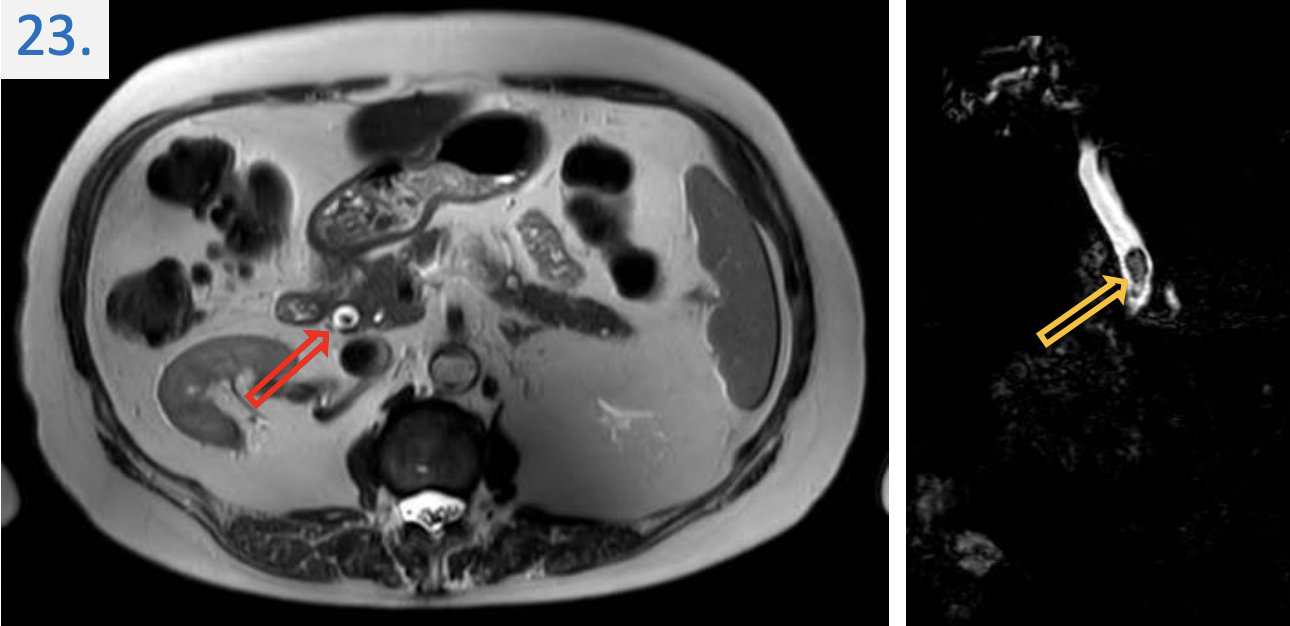

23

24

Diagnosis:

Acute appendicitis